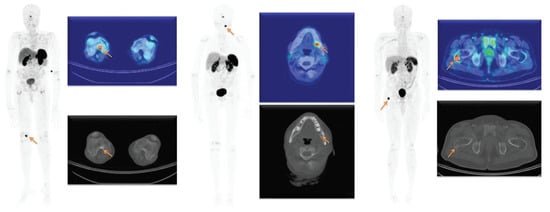

| Renal clear cell carcinoma | 3 ([75,76,77]) | |

| Clifton-Bligh, R. (2013) | [48] | Prospective | 6 | [68Ga]Ga-DOTA-TATE PET/CT, 103–226 MBq, 45–60 min | DOTATATE detected PMT in all 6 cases. 5/6 made full clinical recovery after resection. Patient with symptoms with residual on follow up PET. |

| Juvenile angiofibroma | |||||

| Gronkiewicz, Z. (2016) | [67] | Prospective | 6 | [68Ga]Ga-DOTA-TATE PET/CT (Siemens Biograph 64) 120–160 MBq, 60 min | DOTATATE showed uptake in areas matching the pathologic tissue in juvenile angiofibroma. |